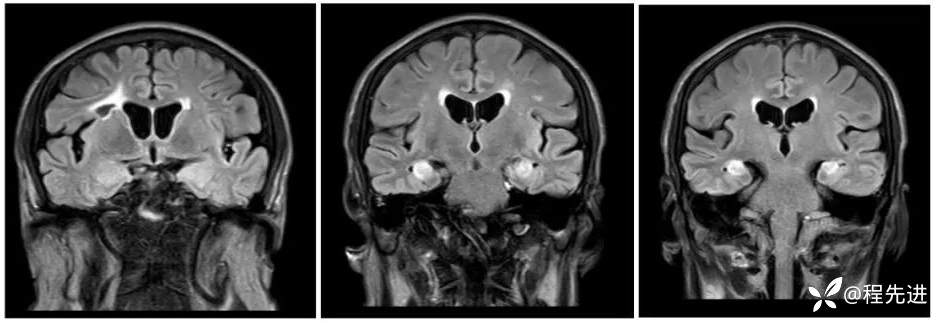

MRI平扫+增强:

FLAIR:

T1增强冠状位:

FLAIR增强: